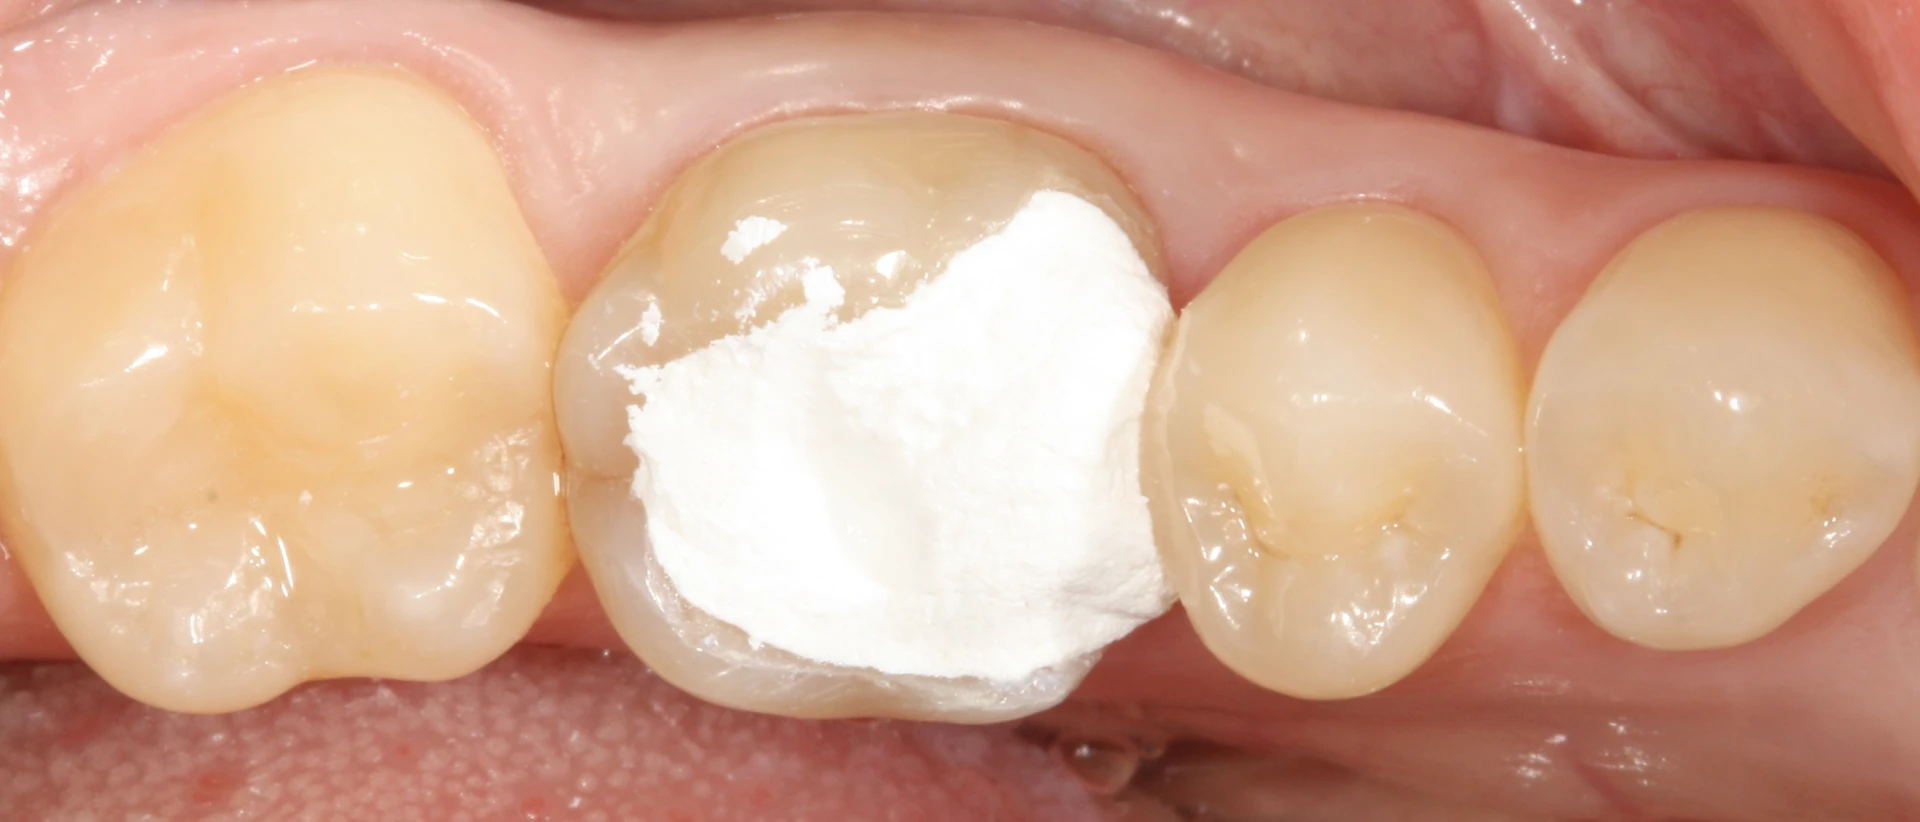

如果您的牙齿填充物脱落了,一定要来我们的诊所找医生,这样我们就可以找到一个长期的解决方案。牙齿填充物缺失的治疗取决于在牙齿中发现了什么。我们一定要去除牙齿填充物的破损部分,并评估剩余的牙齿组织。

如果清洁后蛀牙范围不是太大,可以重新补牙。如果在牙齿填充物脱落后,牙齿组织严重缺失,可以做嵌体补牙或牙冠。如果蛀牙很深,可能需要补牙或进行根管治疗。